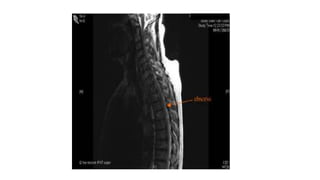

MRI

•Assessment of extradural abscesses / subligamentous spread.

MRI •Assessment of extraduralabscesses / subligamentous spread. •Skip lesions •Spinal cord involvement.